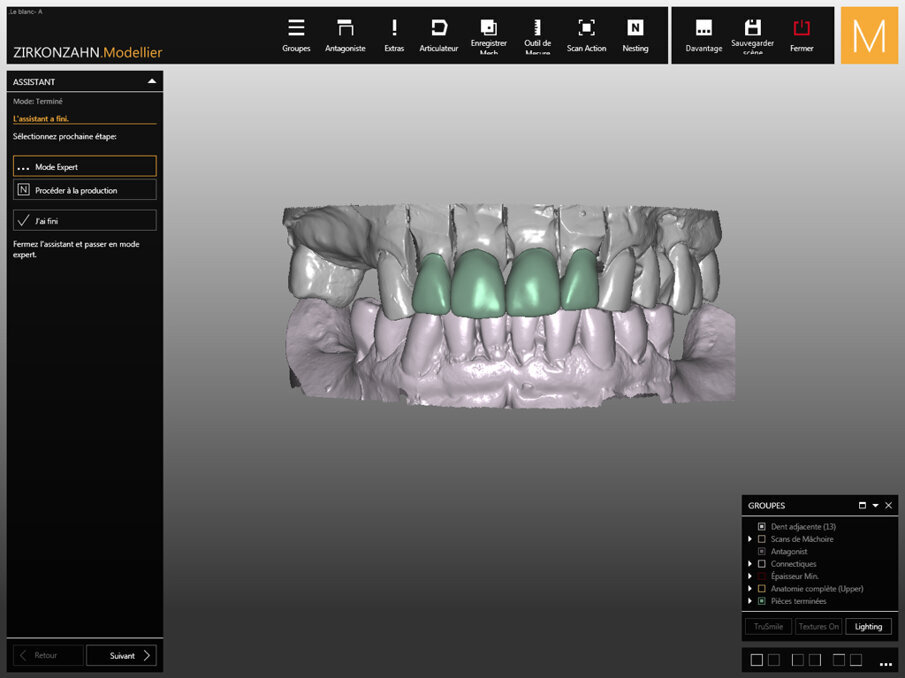

Fig. 6: Digital wax-up of the crowns.

Captured four days earlier, Figure 6 shows the digital wax-up performed in Zirkonzahn.Modellier software (Zirkonzahn). For the dental technician, the main difficulty was rethinking the anatomy of the maxillary incisors while restoring the initial shape of the teeth. The overall shape of the other teeth gives an overview of the geometric typology of the teeth: round, square, triangular.

All forms are possible, but only one form is suitable for this clinical case. CAD/CAM software allows automatic guidance in obtaining a harmonious shape. Then the laboratory technician will take control and proceed individually to bring human touches to a computer system.